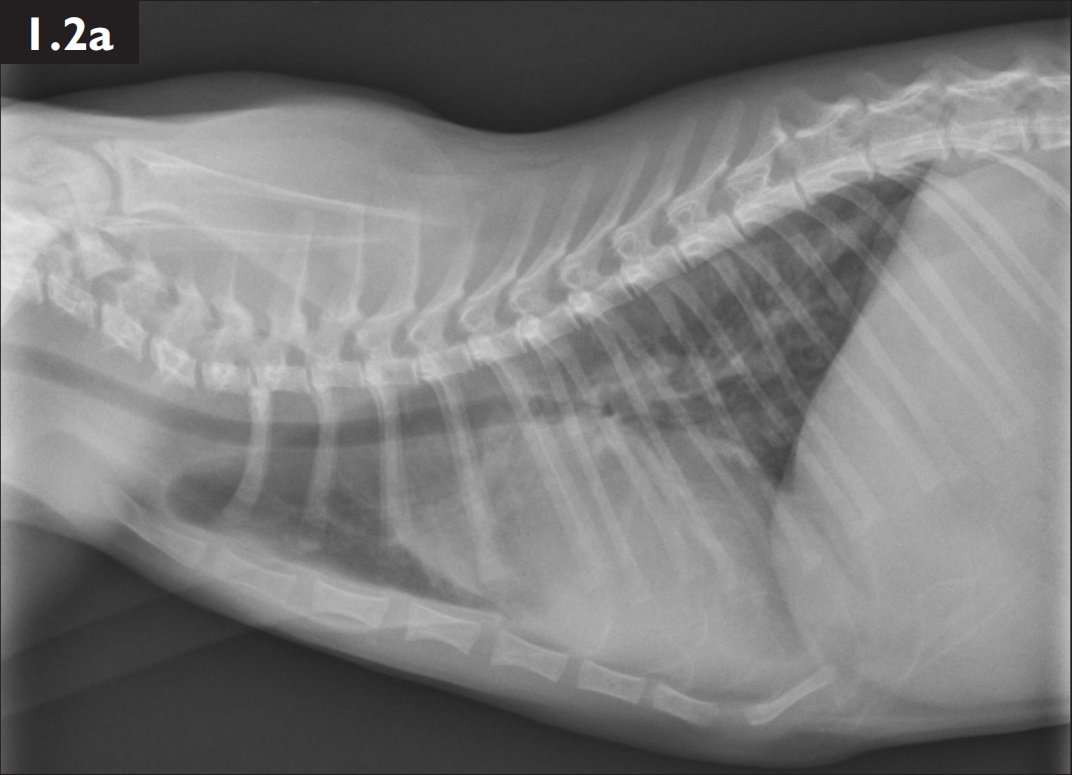

翻译:祁海丽;校对:石慧16 A 6-year-old castrated male Maine Coon cat presents with severe r...